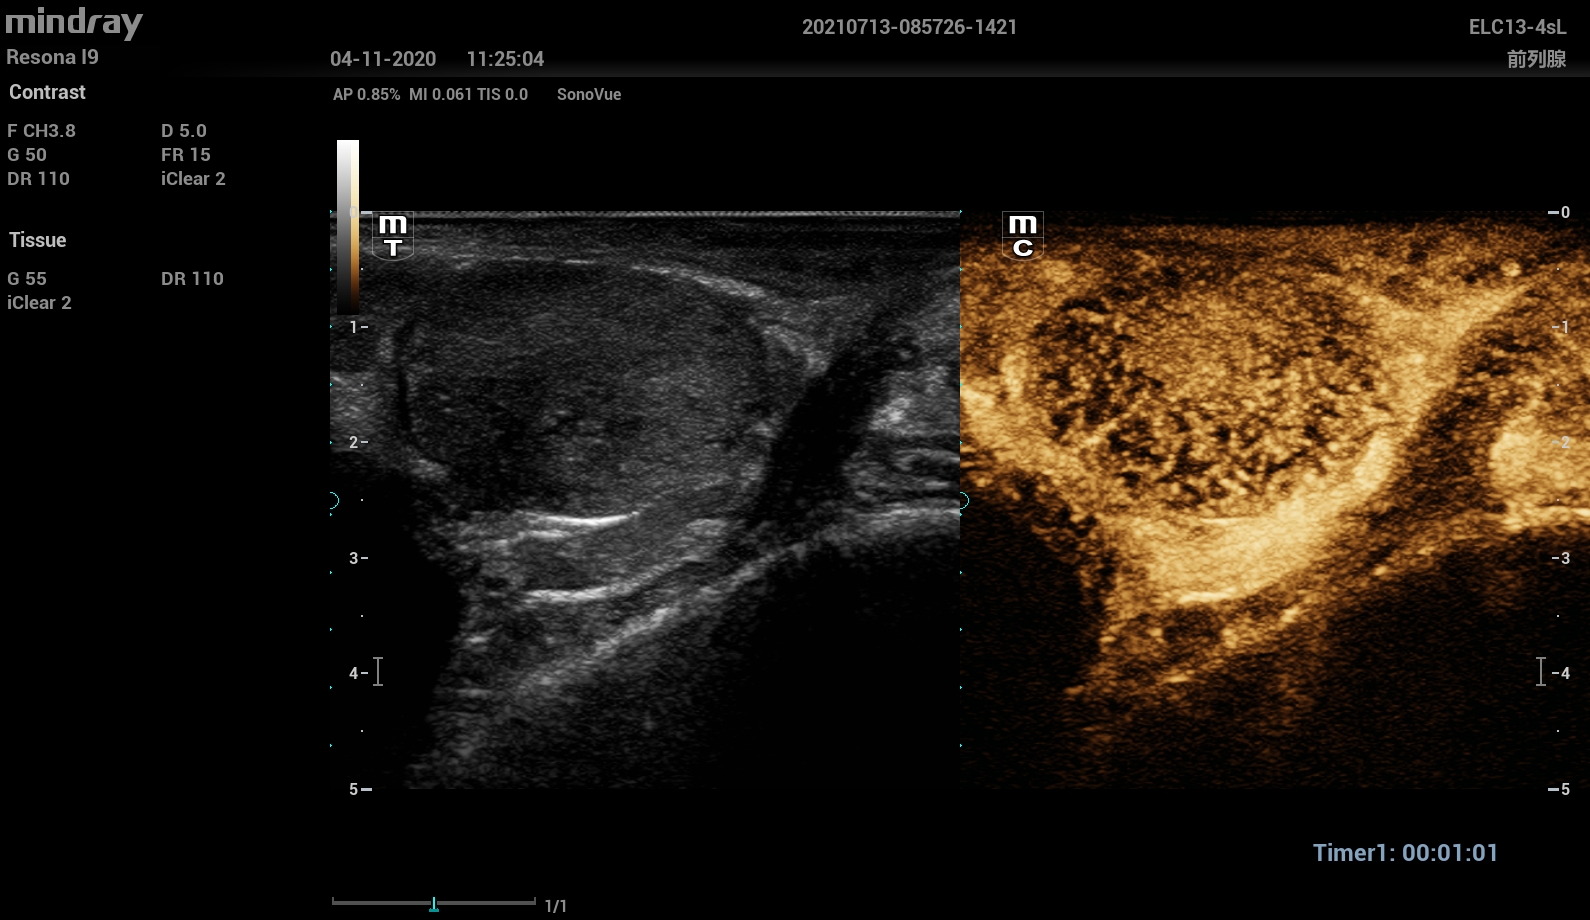

-Урологии (Urology package).